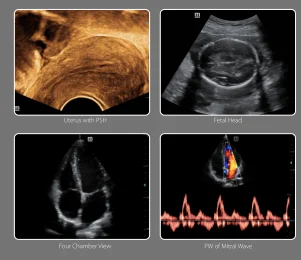

Phase Shift Harmonic

Phase Shift Harmonic (PSH) Imaging, commonly known as Purified Harmonic Imaging, plays an important role in ultrasonic non-linear imaging. The PSH technique enables reduced noise, resulting in images with higher contrast resolution.

4D Imaging&iPageTM

For better obstetric diagnosis, the DC-30 delivers practical and valuable 3D/4D images. With iPage"" (multi-slice view) function, different views of fetal structures are much easier to acquire from one set of volume data.